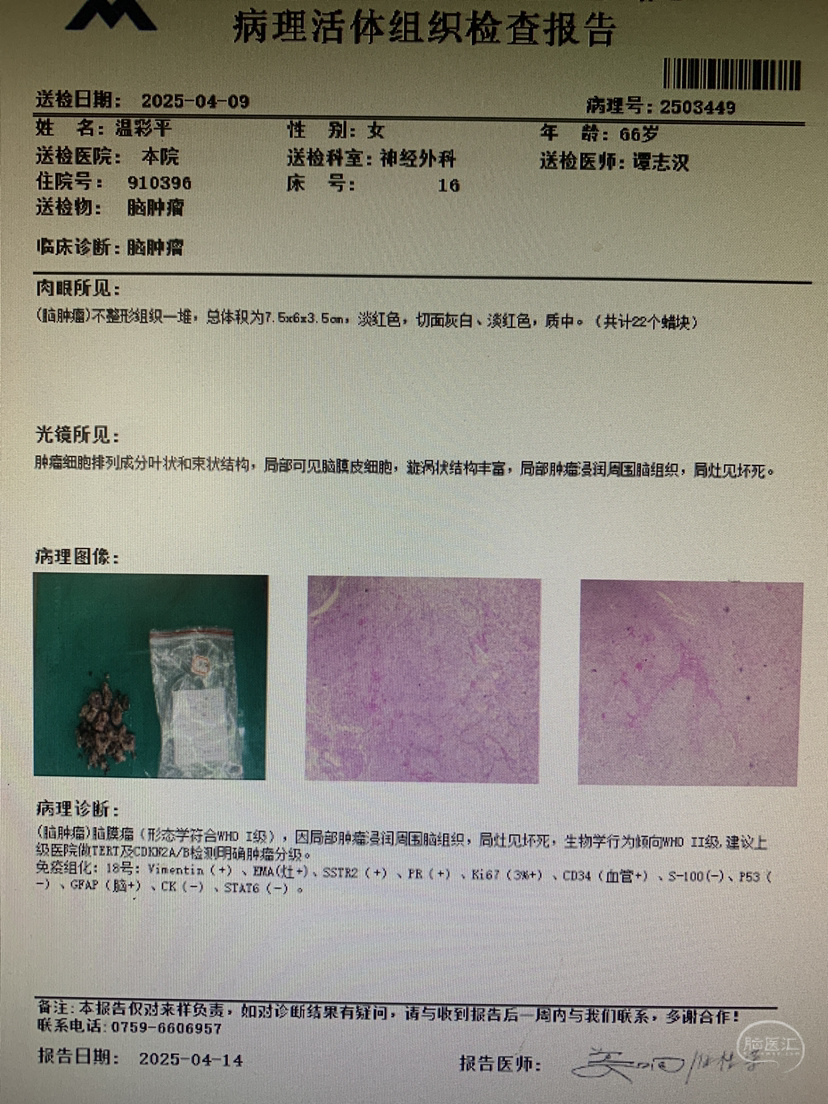

病例二:女,66岁,发现颅内占位5年,意识不清5天坐轮椅来诊。既往史无特殊。

术前CT